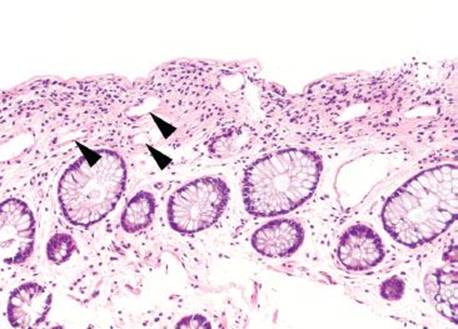

Figure 4.53 Ischemic colitis pattern, early. Lamina propria hemorrhage (arrowheads) is present.

Decreased blood flow and lack of oxygen to the GI tract result in necrosis or tissue damage, causing ischemia. There are several weak points in the colonic blood supply, known as watershed areas, which result from incomplete anastomosis of the marginal arteries and lack of sufficient collateral circulation. These watershed areas are more vulnerable to ischemic injury than other parts of the colon and include the splenic flexure (or Griffith’s point), the rectosigmoid region at Sudeck’s point, and the ileocecal region. Among the older population, ischemic disease is typically attributable to atherosclerotic mesenteric vascular disease, but the causes of colonic ischemia are many (Table 4.2). The histologic findings are dependent on the timing of the ischemic event (Figs. 4.52–4.63). Early and minimal injury, for example, occurs first as degeneration and sloughing of superficial epithelial cells, edema, and vascular congestion. Later, the epithelial cells become markedly attenuated and the crypts appear compressed and atrophic (“microcrypts”) as the lamina propria swells and hemorrhages. Within 5 hours of total acute vascular occlusion, almost the entire intestinal wall appears necrotic. These changes are devoid of acute inflammation until reperfusion occurs. Paradoxically, reperfusion further injures the tissues by introducing oxygen free radical formation,16 the severity of which is dependent on the duration of the preceding hypoxia.